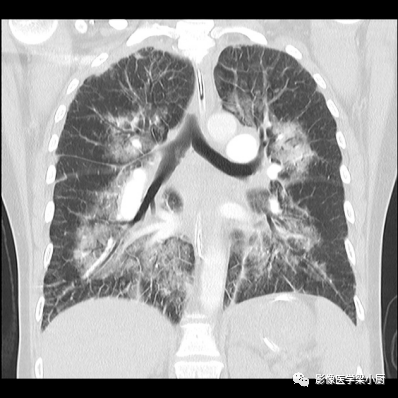

间质性肺水肿CT表现

肺泡性肺水肿CT表现